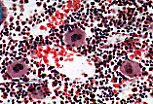

造血淋巴系统